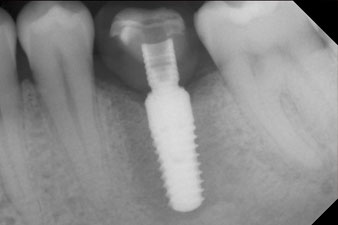

After healing of the soft tissue, the implant stability was measured again before delivery of the prosthetic restoration.

Both values were virtually unchanged and were between the medium and the high range – where the lower value is always used as the reference value that determines the treatment.

Therefore, successful osseointegration and adequate biological stability could be recorded, which enabled an impression to be taken in the same session.